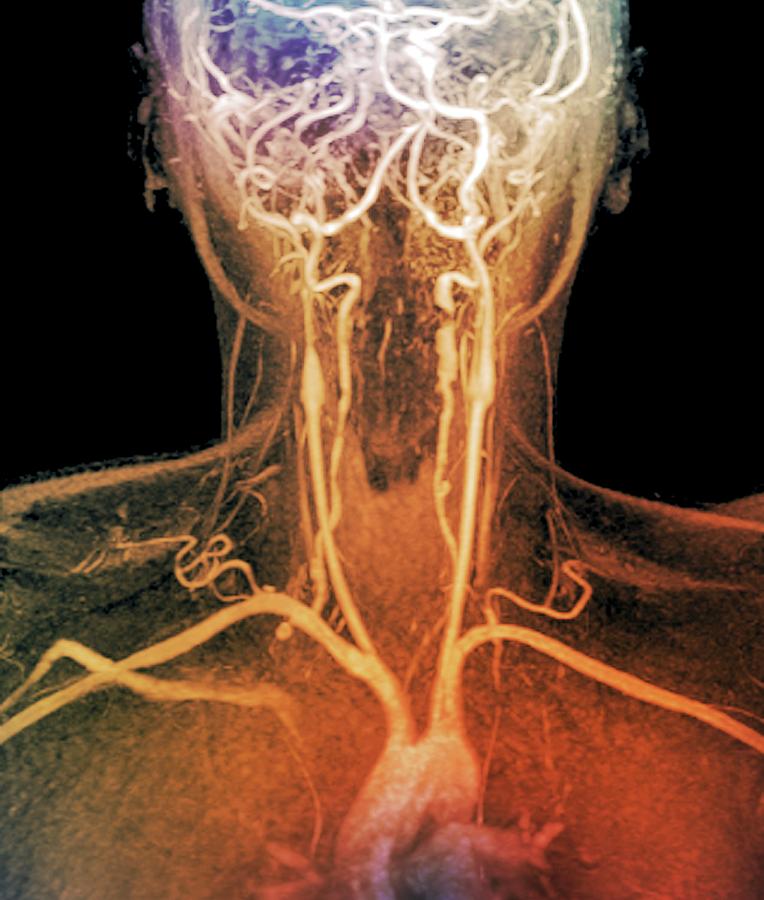

Carotid Artery Thickness..

Bilateral common carotid artery common trunk with aberrant right …

Find Out 36+ Facts Of Arteries In Neck People Did not Share You …